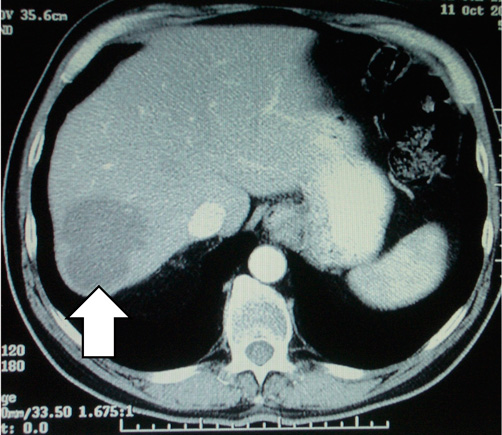

These CT scans show a secondary deposit in the liver from a cancer of the colon, before chemotherapy (left) and after chemotherapy (right). The patient then underwent surgery, but the significant shrinkage made for a lesser operation.